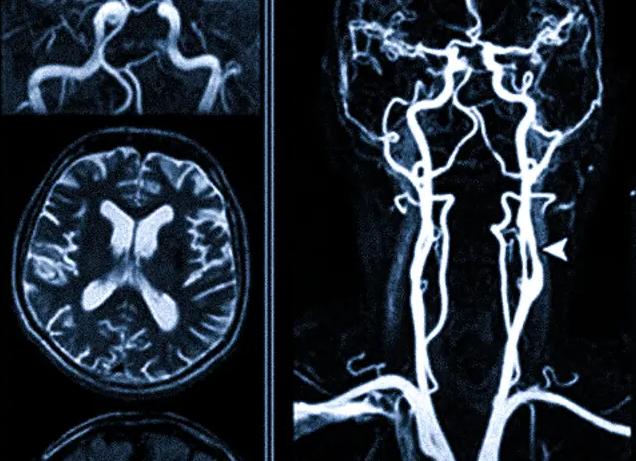

В случае необходимости МРТ сосудов шейного отдела позвоночника и головного мозга (на фото) может использоваться для контроля проведенного лечения и отслеживания изменений, являющихся следствием хирургического вмешательства на артериях и венах.

МРТ сосудов головы и шейного отдела позвоночника

На снимке отчетливо будут видны:

• хрящевые и соединительно-тканные структуры позвоночного столба (межпозвоночные диски, связки, хрящи суставов);

• сосуды разного калибра — от очень крупных артерий и вен до структур мелкого калибра;

• мягкие ткани головы и шеи;

• особенности строение шейного отдела спинного и всех структур головного мозга (оболочки, серое и белое вещество, другие анатомические отделы).

Патология сонной артерии, обнаруженная на МРТ (реконструкция)

При дополнительном введении специального контрастного вещества на снимке будут отчетливо видны артериальные и венозные сосуды, образующие соединенные между собой каротидный и вертебро-базиллярный круги, которые обеспечивают кровоснабжение головного мозга. Изучение сосудов, питающих спинной мозг, при дополнительном контрастировании демонстрирует нарушение нормального кровотока этой зоны.

Кроме того, МРТ ангиография сосудов шеи демонстрирует особенности кровотока по крупным артериям, отходящим от аорты — к ним относят сонные и позвоночные артерии.